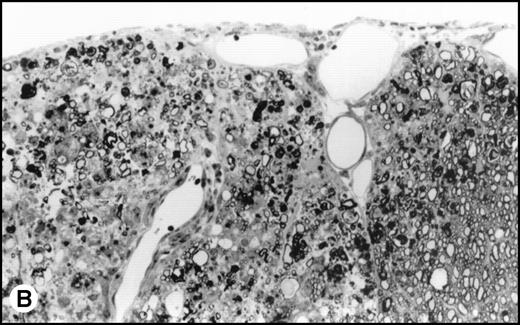

(A) Histology of SJL/J spinal cords from mice infected with TMEV. Section of spinal cord of an SJL/J mouse, 130 days after infection with TMEV. The right anterior column is completely demyelinated and numerous large lipid-laden macrophages are present close to the central sulcus. The gray uniform background reflects conspicuous gliosis in the demyelinated area (1-μm–thick, Epon-embedded section, stained with toluidine blue; original magnification × 220). (B) Section from spinal cord of an SJL/J mouse 130 days after infection with TMEV and after treatment with radiation and BMT. Inflammatory cells are still around the large venule in the parenchyma of the left anterior column, indicating active disease, but many axons are still surrounded by myelin sheaths and gliosis is less prominent (1-μm–thick, Epon-embedded section, stained with toluidine blue; original magnification × 220).

Interestingly, transplanted animals exhibited significantly higher titers of infectious TMEV within the spinal cord than did untreated controls (Fig 4). In transplanted mice, approximately 4-fold more infectious virus was present in the spinal cords than in the nontransplanted mice (12.6 × 103PFU/mg v 3.1 × 103 PFU/mg, P = .004). No viral plaques were found in the brain or spleen of either TMEV-infected group or in any tissues in the uninfected controls. Histologic examination of the spinal cords showed an acute inflammatory infiltrate with less glial scarring in transplanted mice versus a prominent chronic demyelination and gliosis with minimal residual infiltration in nontransplanted mice (Fig5).

Surviving mice displayed significantly diminished immune DTH responses to both virus and myelin epitopes, indicating the effectiveness of the myeloablative therapy (Fig 2). The acute neurologic deterioration correlated with an increased CNS viral load (Fig 4). Histologic evaluation (Fig 5) showed a predominance of acute gray matter inflammation in transplanted mice compared with predominant white matter demyelination in untreated animals. The slightly exacerbated clinical disease course, increased CNS virus levels, and pattern of histology are consistent with an exacerbation of direct viral cytopathology, not immune-mediated CNS damage. This finding is similar to that previously reported by Lipton and Dal Canto,11 who showed that high-dose cyclophosphamide or antithymocyte serum administered shortly after virus infection prevented TMEV-induced immune-mediated demyelination, but resulted in a mortality rate of 77% to 88%. Thus, severe immunosuppression of TMEV-infected animals is capable of causing fatal neurologic consequences that were also likely due to uncontrolled virus growth.